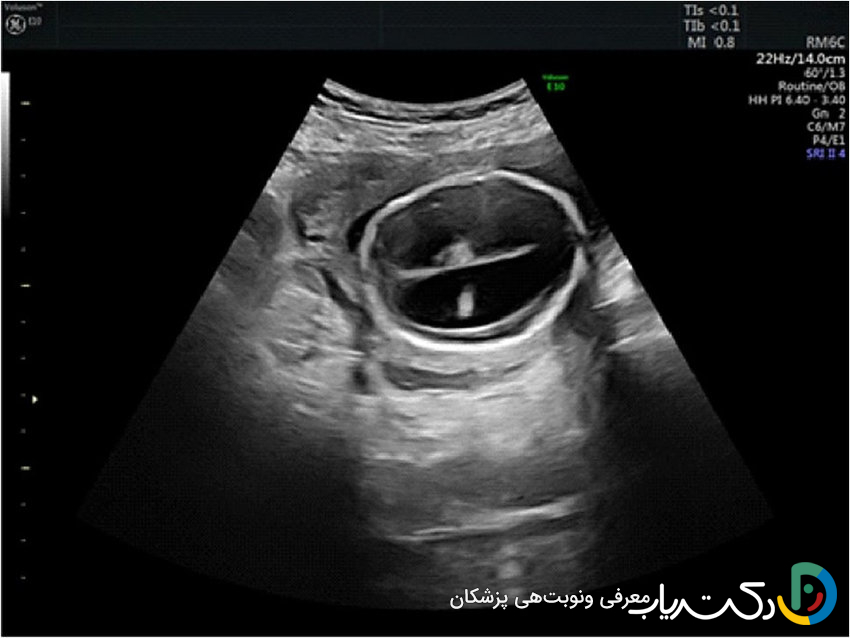

- ونتریکولومگالی: کلیدیترین یافتهای که در سونوگرافی شک به هیدروسفالی را برمیانگیزد، ونتریکولومگالی یا بزرگ شدن بطنهای جانبی مغز است. رادیولوژیست عرض دهلیز بطنهای جانبی را اندازهگیری میکند.

- اندازهگیری طبیعی: کمتر از ۱۰ میلیمتر.

- ونتریکولومگالی خفیف: بین ۱۰ تا ۱۵ میلیمتر.

- ونتریکولومگالی شدید: بیشتر از ۱۵ میلیمتر.

- اهمیت یافتهها و علائم مرتبط: تشخیص ونتریکولومگالی همیشه به معنای هیدروسفالی نیست، اما یک زنگ خطر جدی است. متخصص سونوگرافی به دنبال سایر علائم مرتبط نیز میگردد، مانند عدم وجود ساختارهای دیگر مغزی (مثل کورپوس کالوزوم) یا ناهنجاریهای ستون فقرات (مانند اسپاینا بیفیدا). این یافته نیازمند بررسیهای بیشتر مانند سونوگرافیهای هدفمند و دقیقتر، MRI جنین برای ارزیابی بهتر آناتومی مغز و مشاوره ژنتیک است تا علت زمینهای آن مشخص شود.

- تصاویر حاصل: سونوگرافی جمجمه به وضوح اندازه و شکل بطنها را نشان میدهد و میتواند وجود خونریزی ، کیست، آسیب به بافت اطراف بطنها یا سایر ناهنجاریهای بزرگ را مشخص کند.